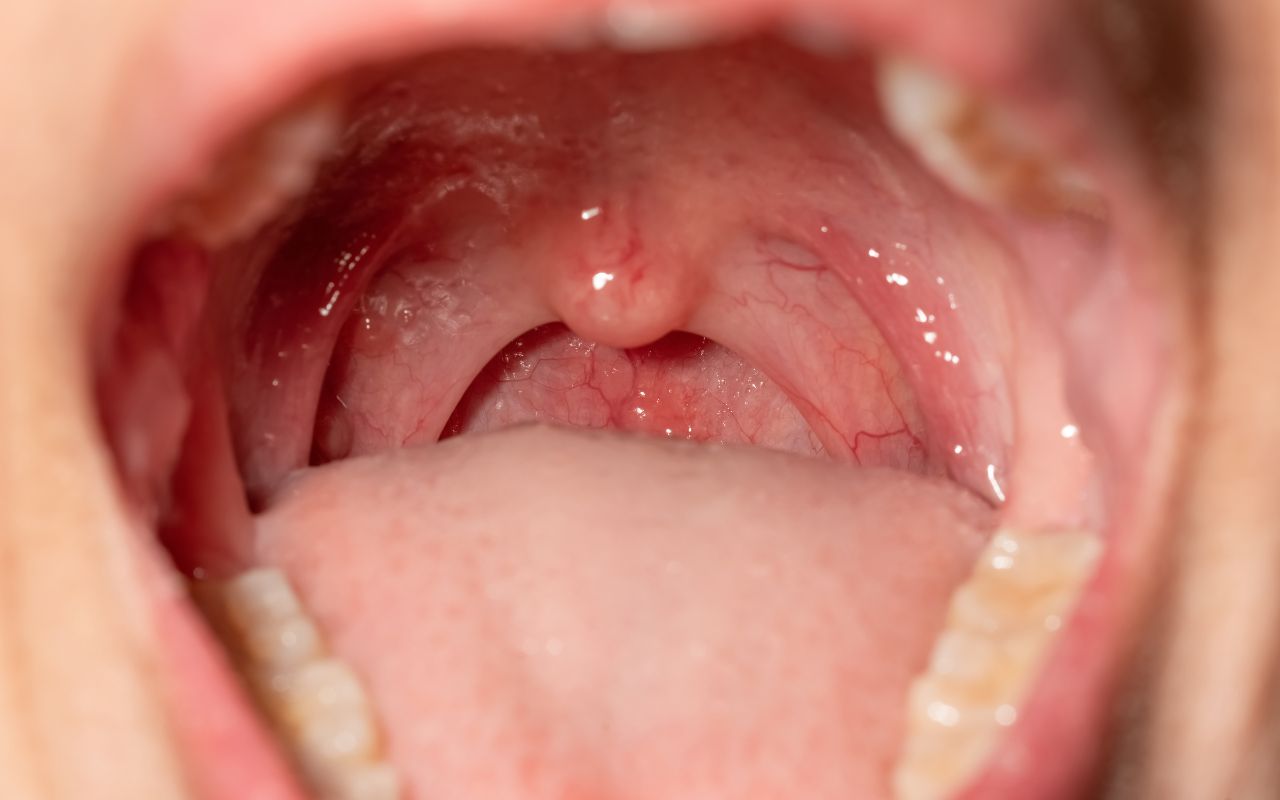

Viêm họng cấp tính là bệnh lý phổ biến, gây ra các triệu chứng đau rát, khó nuốt, ho và sốt. Bên cạnh thuốc điều trị, chế độ ăn uống khoa học đóng vai trò then chốt giúp làm dịu cổ họng, giảm đau và tăng cường hệ miễn dịch, hỗ trợ cơ thể nhanh phục hồi.